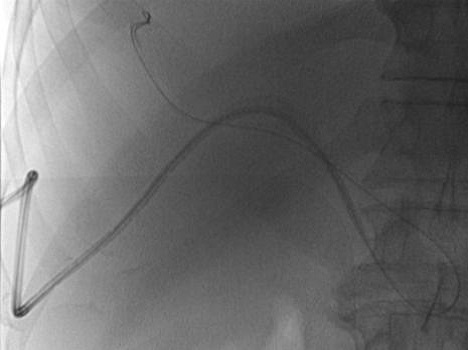

指PTCD引流管脱离胆道引流的位置 PTCD引流管脱出包括全脱出和半脱出 引流管半脱位 引流管全脱位 PTCD引流管全脱位

指PTCD引流管脱离胆道引流的位置

PTCD引流管脱出包括全脱出和半脱出

引流管半脱位

导管没有脱位,体外的引流管进入

体外引流管进入

引流管全脱位

PTCD引流管全脱位